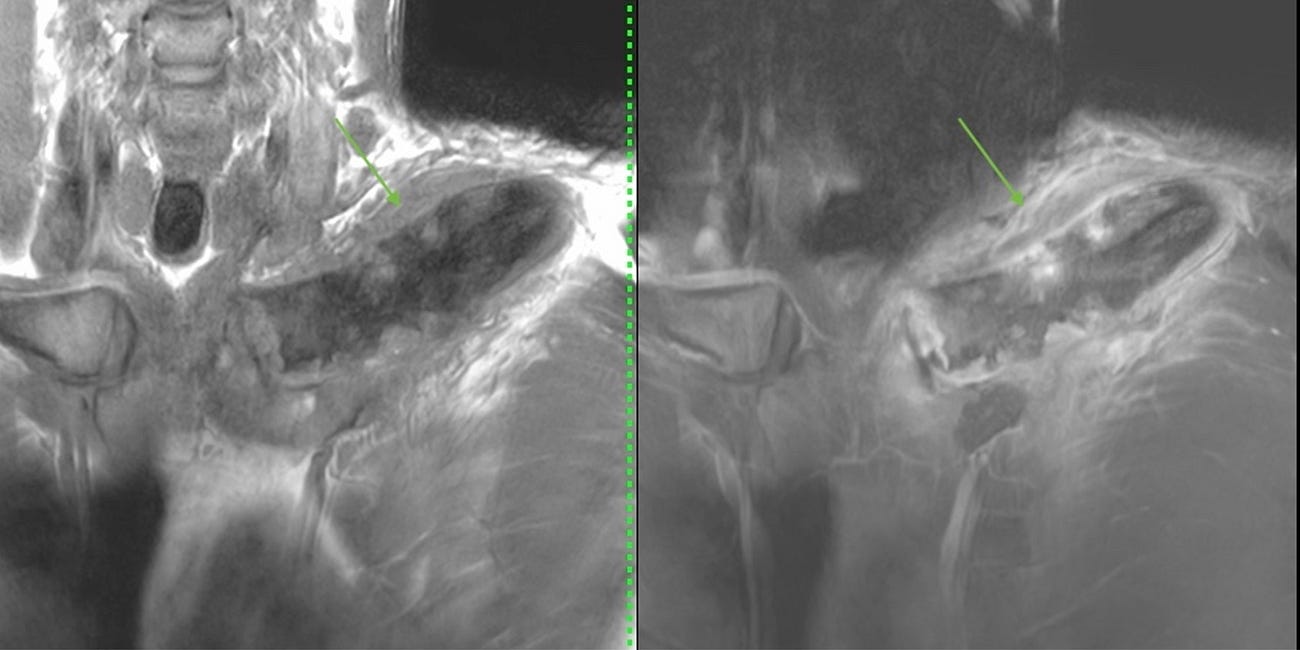

COD 136 - A Swollen Metatarsal Bone

10-years old girl with a left 1st metatarsal lesion

10-years old girl with a left 1st metatarsal lesion with marrow edema, but no cortical break or extra-osseous soft tissue mass or collection.

A biopsy showed inflammation, ruled out tumor, with no evidence of obvious infection.

A whole body MRI was done to clinch the diagnosis.